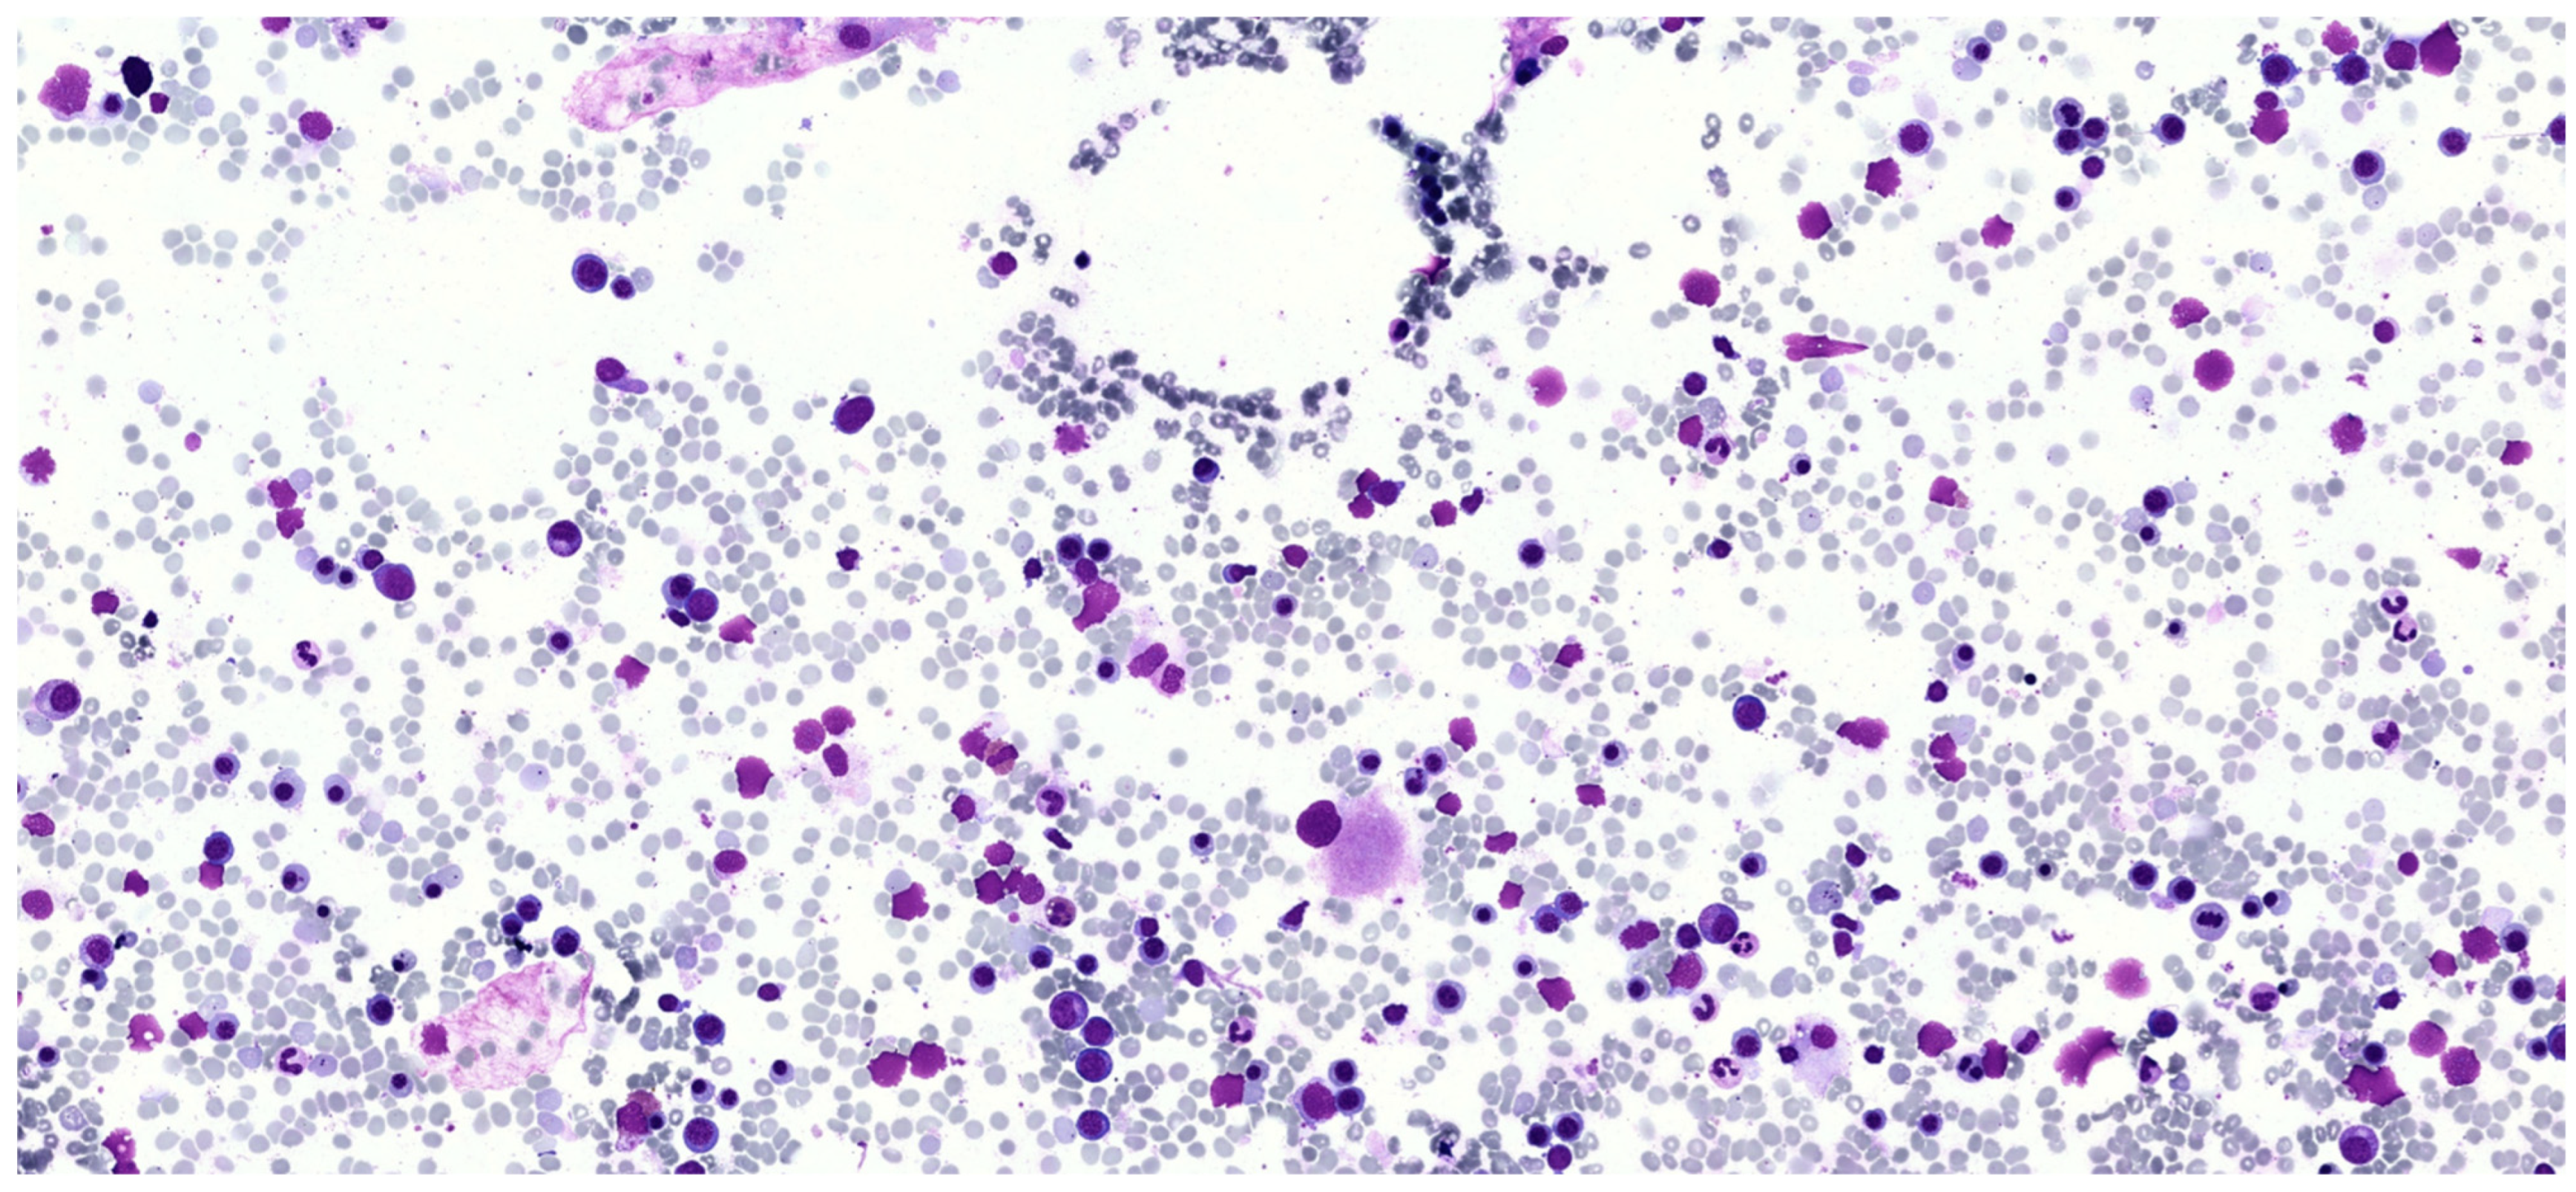

Diagnostic Challenges in a Young Man with a Suspected Mast Cell Disorder, Dysplastic Bone Marrow Morphology, and a ZRSR2 Mutation

2. Case Report